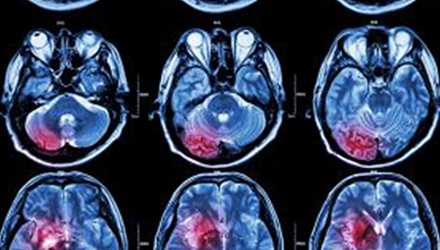

在這項(xiàng)研究中,研究人員使用功能核磁共振成像(fMRI)觀察大腦中血液含氧量的變化。研究人員首先研究了耳鳴患者和無(wú)耳鳴者的大腦活動(dòng),其目的是比較兩組受試者大腦處理情緒的方式。

在功能磁共振成像檢查中,受試者分別聽(tīng)30種“愉悅”的聲音、30種“不愉快”的聲音和30種“中性”的聲音。這些聲音包括小孩咯咯笑,嬰兒啼哭,以及熱水壺?zé)_(kāi)的聲音。

功能磁共振成像的結(jié)果顯示,當(dāng)暴露于情緒性聲音下,耳鳴患者大腦不同區(qū)域的活動(dòng)比沒(méi)有耳鳴者的活動(dòng)更強(qiáng)烈。接著,研究人員進(jìn)行了更深入的研究:耳鳴患者的大腦活躍性和耳鳴嚴(yán)重程度的關(guān)系。

調(diào)查結(jié)束后,再進(jìn)行功能核磁共振成像檢查。第二輪功能核磁共振成像顯示,那些耳鳴較輕的患者實(shí)際上使用了大腦不同的區(qū)域來(lái)處理情緒信息。

傳統(tǒng)觀點(diǎn)認(rèn)為,大腦中的扁桃體是處理情緒的關(guān)鍵,但此次研究發(fā)現(xiàn),那些不被耳鳴困擾的患者實(shí)際上使用更多大腦額葉來(lái)處理情緒。這類(lèi)患者額葉活動(dòng)更顯著的原因是,額葉通常更多地用于注意力、計(jì)劃和沖動(dòng)的控制。